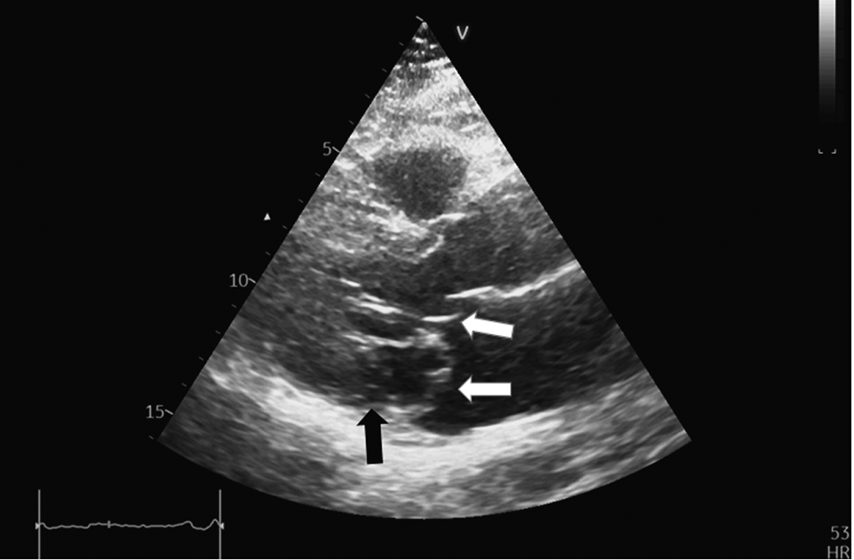

EchoCG was performed using modern technologies of three-dimensional image reconstruction and Mitral Valve Quantification model on Vivid-9 ultrasound device. The results showed that mitral regurgitation was mild [16]. The effective regurgitation orifice area was 0.18 cm2, and the regurgitation volume was 20 mL. Both mitral valve leaflets were myxomatous, thickened, and prolapsed up to 8 mm into the LA cavity (Fig. 1–3). The prolapse was polysegmental (Fig. 4). Signs of MAD (absence of myocardial tissue up to 9 mm under the posterior mitral valve leaflet) were revealed (Fig. 1, 2).

Fig. 1. Parasternal long-axis view of the left ventricle. Systole. White arrows indicate elongated and thickened mitral valve leaflets prolapsing into the left atrial cavity. The black arrow indicates the disjunction area

Fig. 2. Parasternal long-axis view of the left ventricle. Diastole. The elongated and thickened mitral valve leaflets (predominantly posterior) are visible. The black arrow indicates the disjunction area below the posterior mitral valve leaflet.